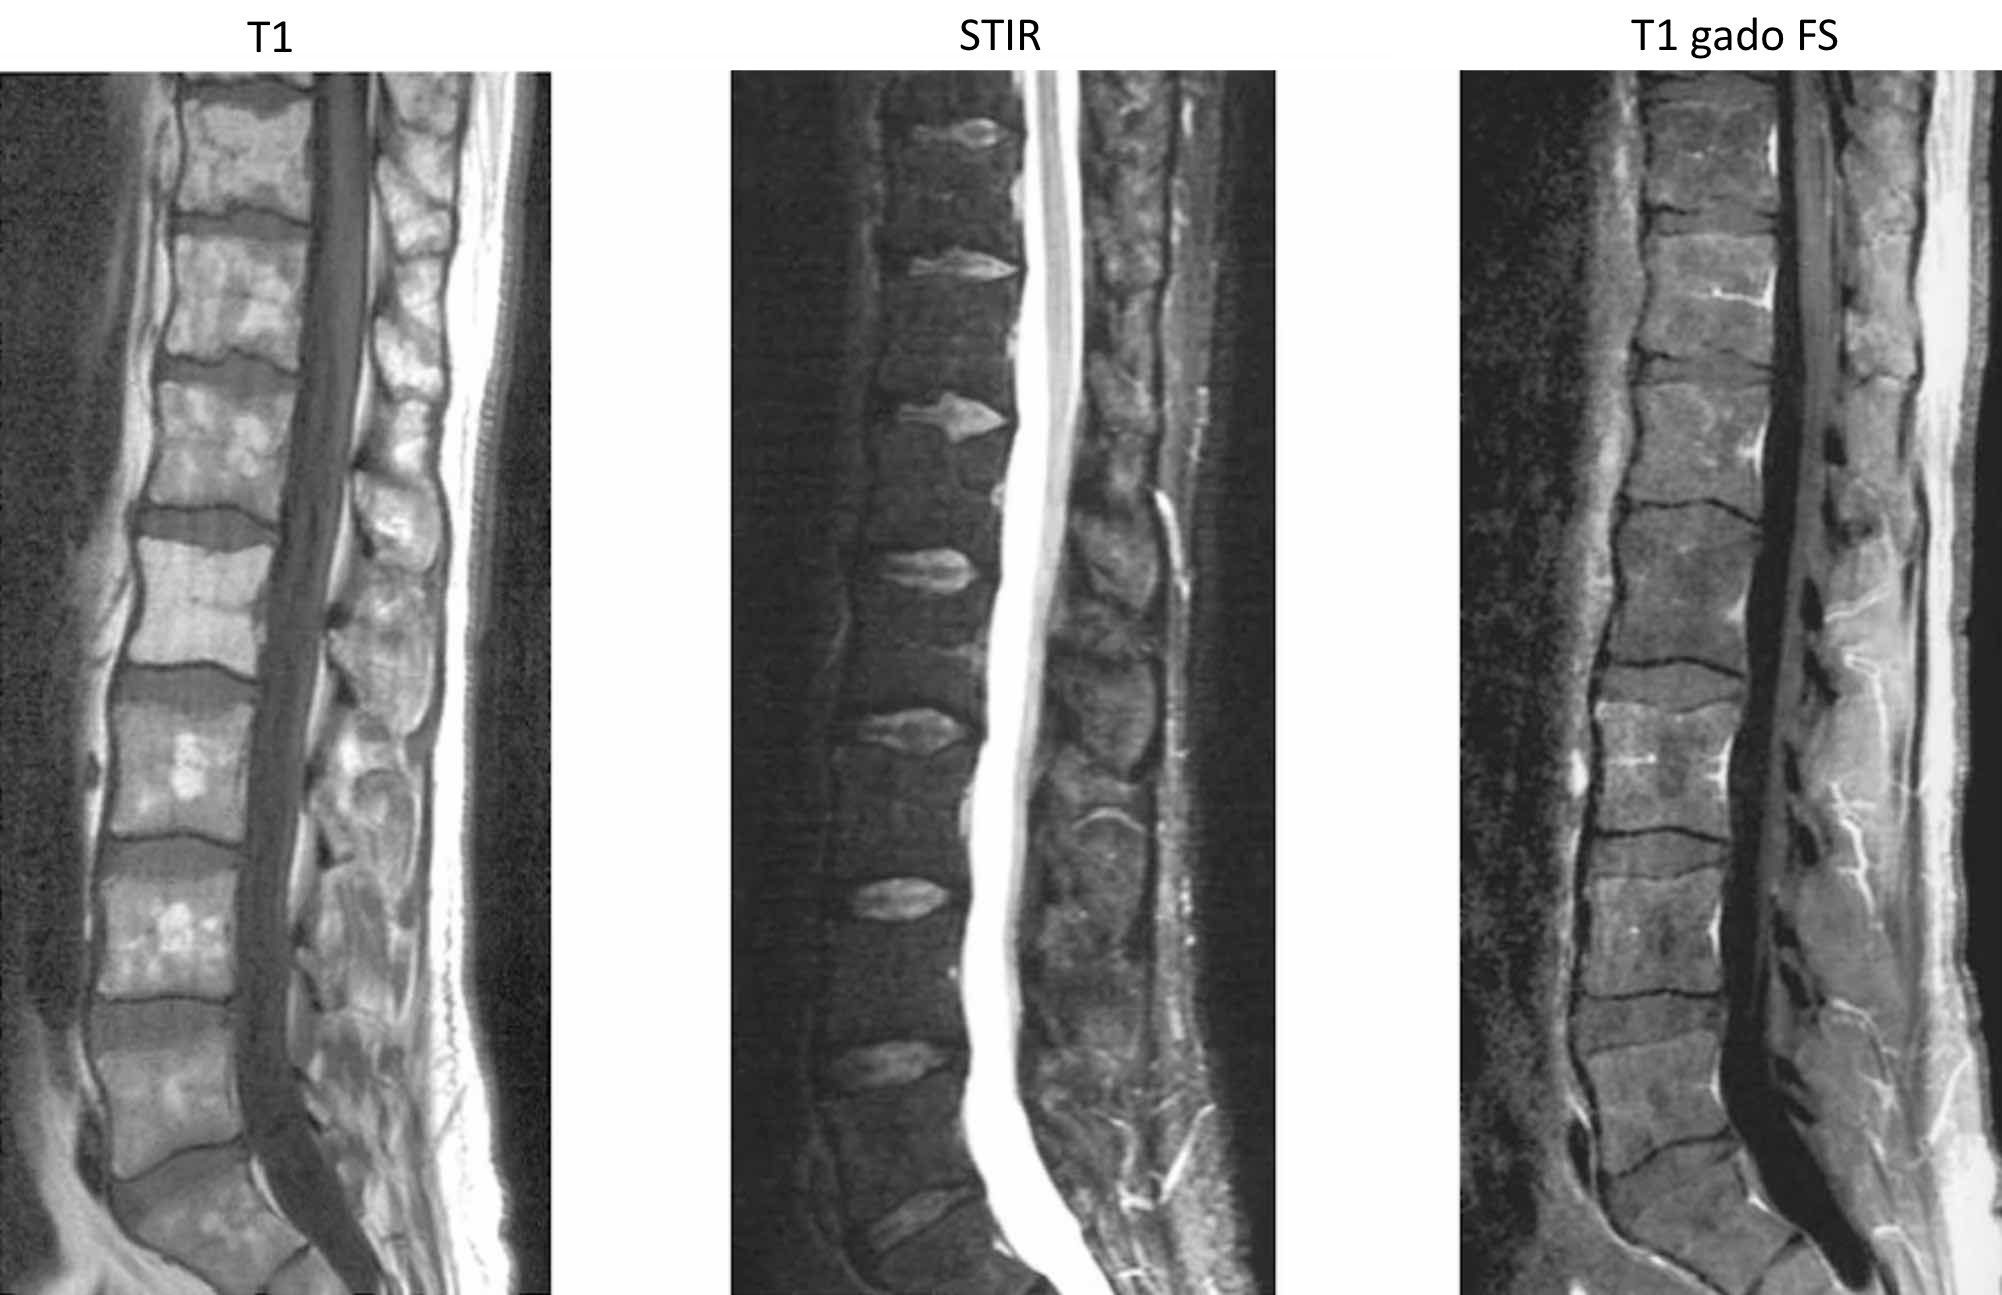

Discopathie dégénérative prédominant en avec remaniements de type Modic .

Modic I = inflammatoire « œdémateux », II = involution graisseuse, III = fibrose

Modic I = inflammatoire « œdémateux », II = involution graisseuse, III = fibrose

aspect normal moelle jaune (graisse) = HT1 avec ilôts de moelle rouge (hématopoïétique) = hT1

aspect normal moelle jaune (graisse) = HT1 avec ilôts de moelle rouge (hématopoïétique) = hT1

moelle en hT1 par rapport au disque et HSTIR par rapport aux muscles

moelle en hT1 par rapport au disque et HSTIR par rapport aux muscles

=> à confronter au bilan biologique avec électrophorèse des protéines sériques